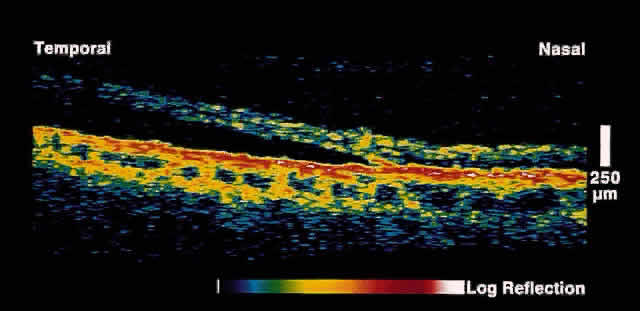

The diagnosis and management of glaucoma remains a difficult clinical problem. Intraocular pressure measurements do not always adequately predict the extent of glaucomatous change. Optic nerve head and gonioscopic evaluation by slit-lamp biomicroscopy is subjective. Visual field loss and optic nerve head cupping are late clinical findings, detected only after up to 50% of retinal nerve fibers have been lost.

OCT, because of its high resolution, is able to detect nerve fiber layer thinning before the onset of visual changes.21 Nerve fiber layer thickness, as measured by OCT, has been shown to correspond to visual function. As expected from the histology of the peripapillary retina, the nerve fiber layer is thickest in the inferior and superior quadrants. The nerve fiber layer has been demonstrated to be significantly thinned in areas corresponding to visual field loss.

Typically, the scans are performed radially around the optic nerve for 360° using two radii of curvature (2.25 and 3.37 mm), and the nerve fiber layer thickness is plotted schematically (Fig. 16). Normal nerve fiber layer thickness is a mean of 148.6 microns for superior nerve fibers, 143.5 microns for inferior nerve fibers, 66.9 microns for temporal nerve fibers, and 117.2 for nasal nerve fibers. The direct measurement of the nerve fiber layer thickness by OCT is an objective assessment of glaucomatous progression. OCT shows promise in the early diagnosis of glaucoma before visual field defects, optic nerve head changes, and ophthalmoscopically visible nerve fiber layer loss are evident.

Fig. 16. Circular OCT image of a normal eye taken in cylindrical section around the optic nerve head. Note the thicker nerve fiber layer superiorly and inferiorly.